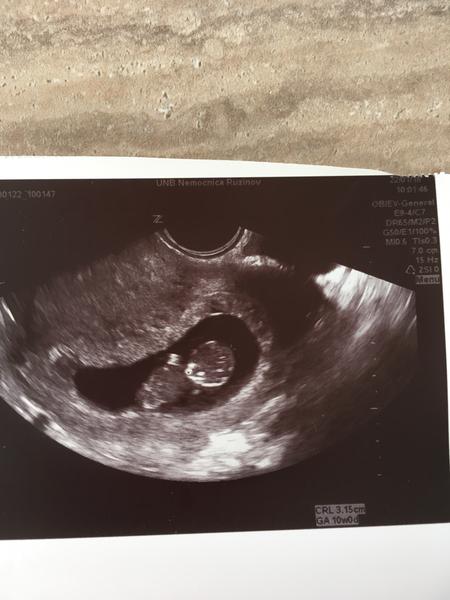

Začiatok 11 tt